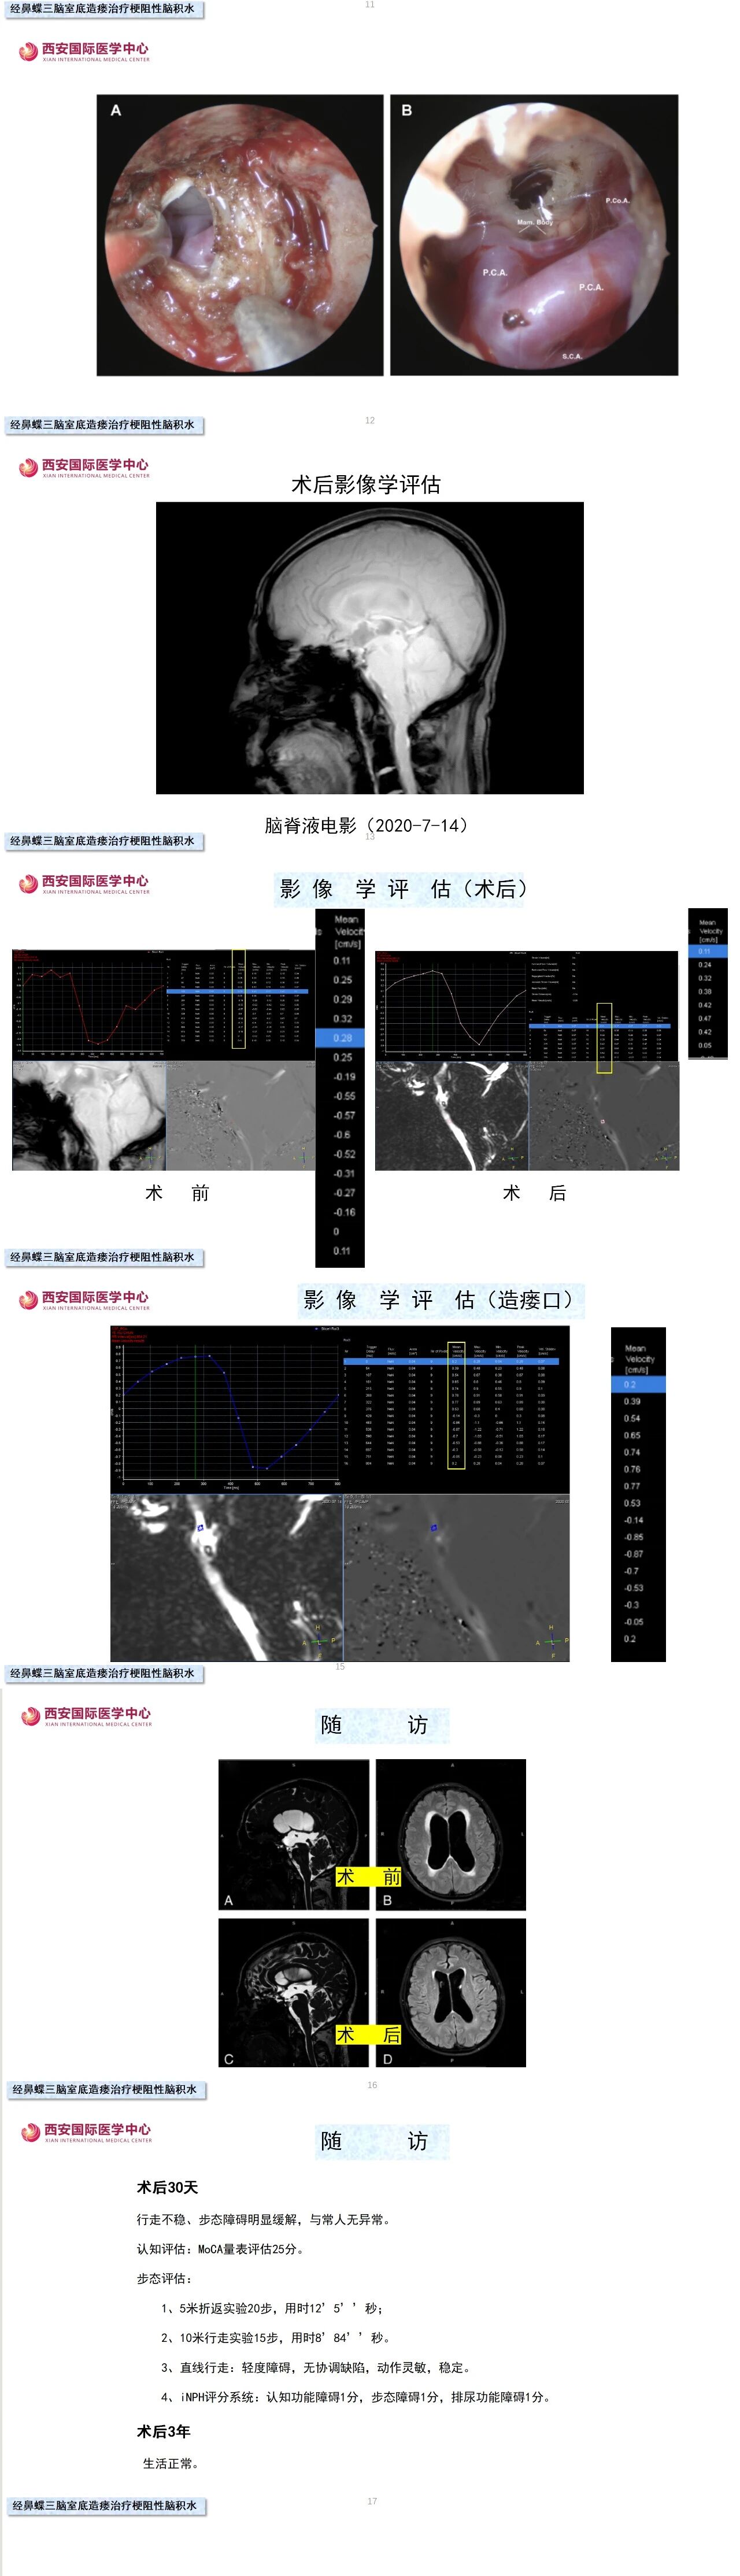

第三脑室底造瘘术是梗阻性脑积水公认的首选治疗方式。随着显微镜、内镜技术的发展,以及微创理念的不断更新,从传统的经额叶皮层入路逐渐转变为经纵裂胼胝体入路,再到我们独创的神经内镜经鼻蝶第三脑室底造瘘术,可谓将微创理念发挥到极致,对脑组织几乎无损伤,手术效果满意。